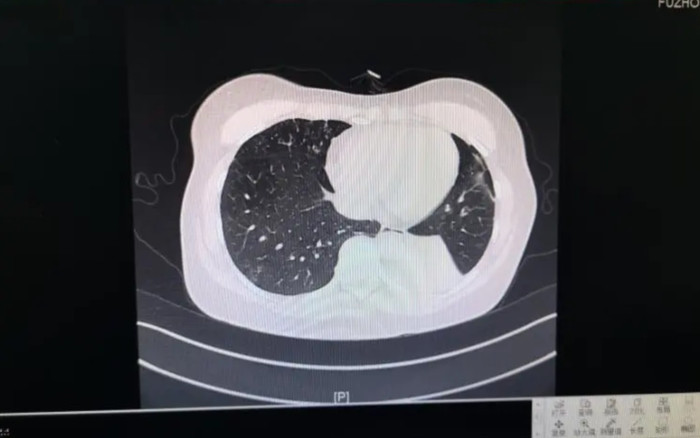

Tháng 6/2024, một trường hợp tương tự cũng xảy ra tại Phúc Kiến. Một người phụ nữ ho kéo dài suốt hai tháng, sau đó được xác định mắc aspergillus phế quản phổi xâm lấn. Kết quả sinh thiết và xét nghiệm bệnh lý cho thấy trong mô tổn thương có chứa số lượng lớn nấm mốc.

Trước đó, một người phụ nữ được chẩn đoán mắc aspergillus phế quản phổi xâm lấn vì chứa số lượng lớn nấm mốc trong cơ thể. (Ảnh: Sohu)